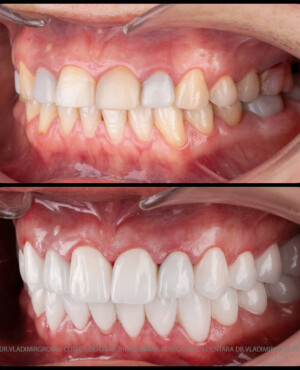

Caz 1

Caz 2

Transformările estetice și impactul reabilitării asupra vieții pacienților

Reabilitarea dentară produce o schimbare vizibilă și profundă în aspectul pacientului, cu efecte pozitive evidente asupra stimei de sine și a calității vieții. Mulți pacienți relatează bucuria redobândirii funcției masticatorii și dispariția complexelor legate de aspectul dentar.